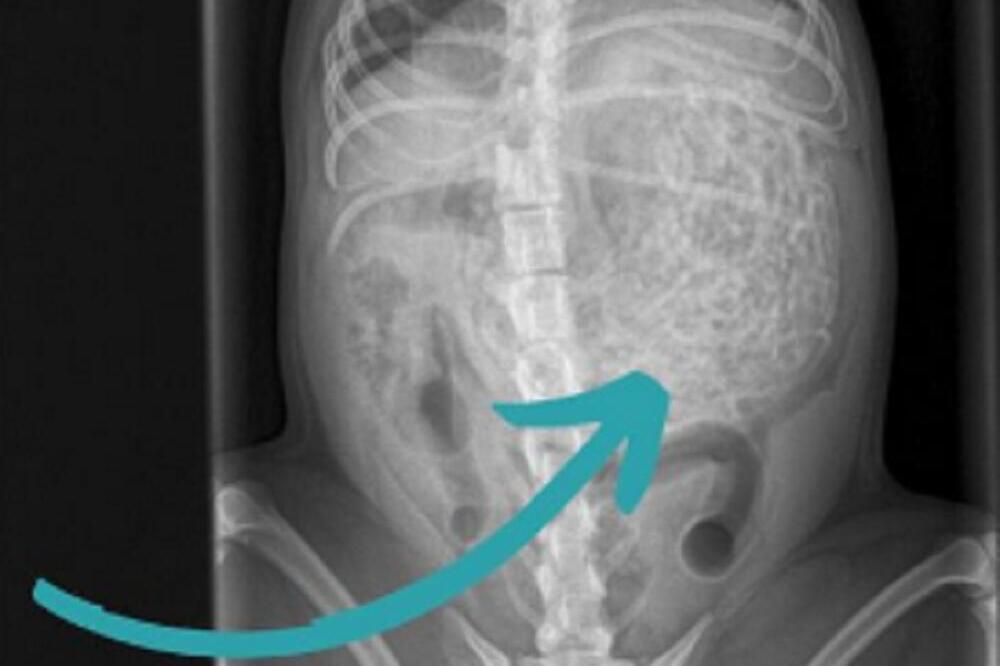

Britanska porodica doživela je pravi šok kada su psa odveli kod veterinara zbog "lošeg osećaja" koji su imali, jer je odjednom postao tih. Tamo je na ultrazvuku otkriveno da je pas pojeo 200 grama gumica za kosu!

Pregled u veterinarskoj ordinaciji pokazao je da pas ima nešto neobično u stomaku, pa su se odmah odlučili na operaciju. Izvađeno mu je oko 60 gumica teških 200 grama, a pas Hem je težak samo šest kilograma.